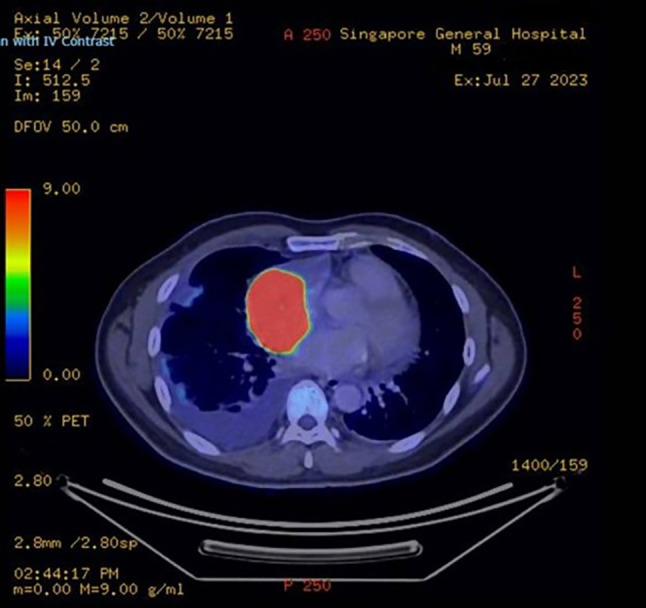

Case report: This case describes a 59-year-old patient who presented with a cardiac mass and exhibited signs of superior vena cava syndrome, including odynophagia, dysphagia, hoarseness, and constitutional symptoms. Subsequent investigations revealed a primary malignant spindle cell sarcoma originating from the pericardium.